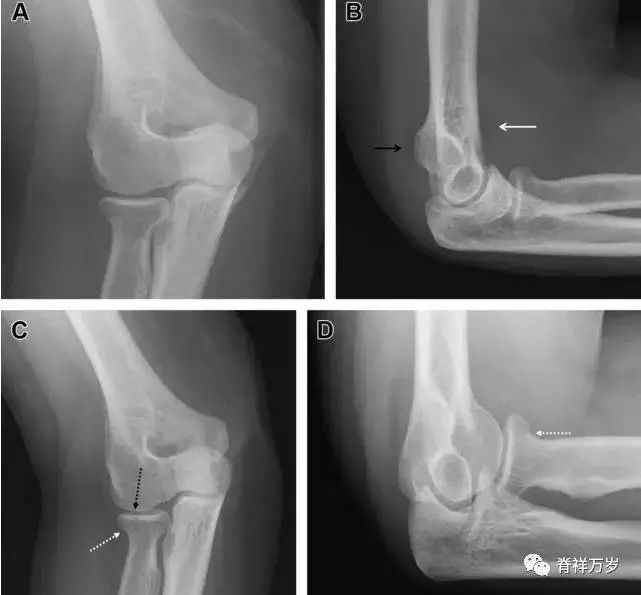

无移位的桡骨头/颈骨折

多发生于摔倒时,手掌撑地,受到轴向、外翻应力所致。常规的前后位片容易漏诊,常需加拍内斜位、外斜位、桡骨头-肱骨小头位片。后脂肪垫可见(位于鹰嘴窝内,一般不可见)和/或前脂肪垫抬高常提示骨性损伤。

图 2 桡骨头骨折。前后位(A)和侧位(B)片示后脂肪垫抬高(黑色箭头),前脂肪垫抬高(白色箭头),呈「帆船征」,其它表现正常;外斜位(C)和桡骨头–肱骨小头位(D)示桡骨头关节内骨折线(虚线黑箭头)累及桡骨颈(虚线白箭头)。

Essex-Lopresti 损伤

Essex-Lopresti 损伤是桡骨头骨折伴有下尺桡关节脱位,导致骨间膜损伤,桡骨短缩。此种损伤,桡骨头骨折的诊断往往是明确的,容易忽视的是下尺桡关节脱位,特别是早期,下尺桡关节的症状不明显,X 线表示也不明显。

图 8 Essex-Lopresti 损伤。前后位(A)和侧位(B)示桡骨头关节内骨折(白色实线箭头);(C~E)伤后 1 个月复诊,患者诉腕关节疼痛,X 线(C,D)发现下尺桡关节脱位,(E)CT 进一步证实损伤的存在。